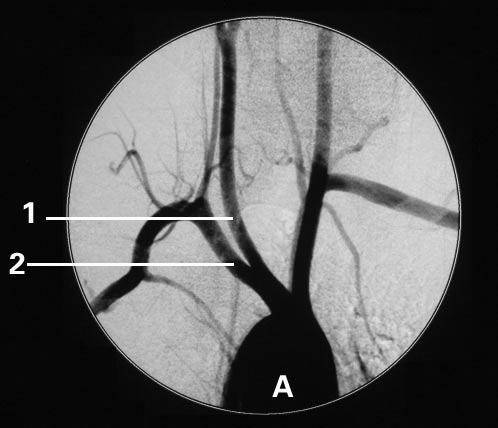

脑梗死是一种常见的临床病症,多发性腔隙性脑梗死与单发性腔隙性脑梗死一样,都是脑梗死(脑血栓、脑栓塞、腔隙性脑梗死、多发性脑梗死、短暂性脑缺血发作)的一种特殊类型。其多发生在基底节区,是在高血压、动脉梗化的基础上,脑深部的微小动脉发生闭塞,引起脑组织缺血性软化病变,属于脑梗死症型中症状最轻微的,也是唯一一种能够通过可靠用药、饮食调节、康复锻炼、控制血压和血脂等综合性治疗措施达到彻底治愈的脑梗死。多数腔隙性脑梗死由于一般发病部位多,病灶面积小,所以又称为多发腔隙性脑梗死。腔隙性脑梗死的临床诊断一般是指直径在15~20毫米以下的新鲜或陈旧性脑深部小梗塞。这些小动脉闭塞后,可引起多个大小不同的脑软化灶,最后形成大大小小的腔隙。